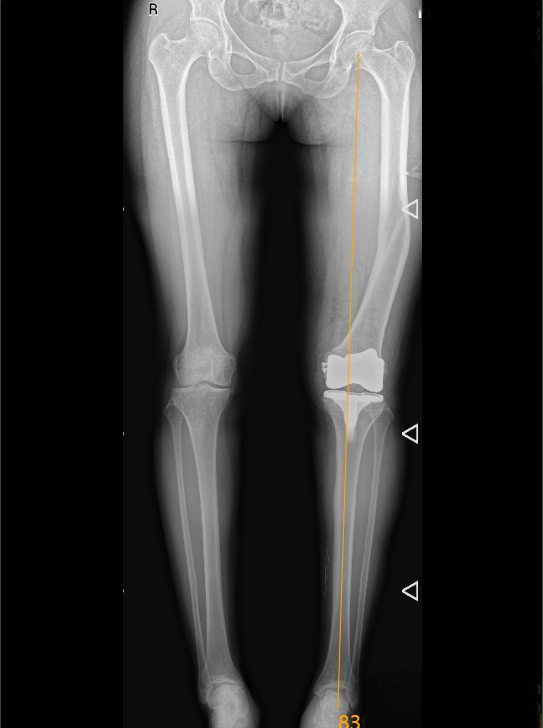

术后复查显示,王女士双下肢的力线恢复正常,膝盖伸直、弯曲都能动态平衡,假体固定得稳稳的。

术中,机器人全程 “导航”,实时评估术中软组织张力与内外侧间隙,骨切割精度达到毫米级,确保假体安装的角度、位置都刚刚好,就像给膝盖拼精密拼图,每一步都不差。